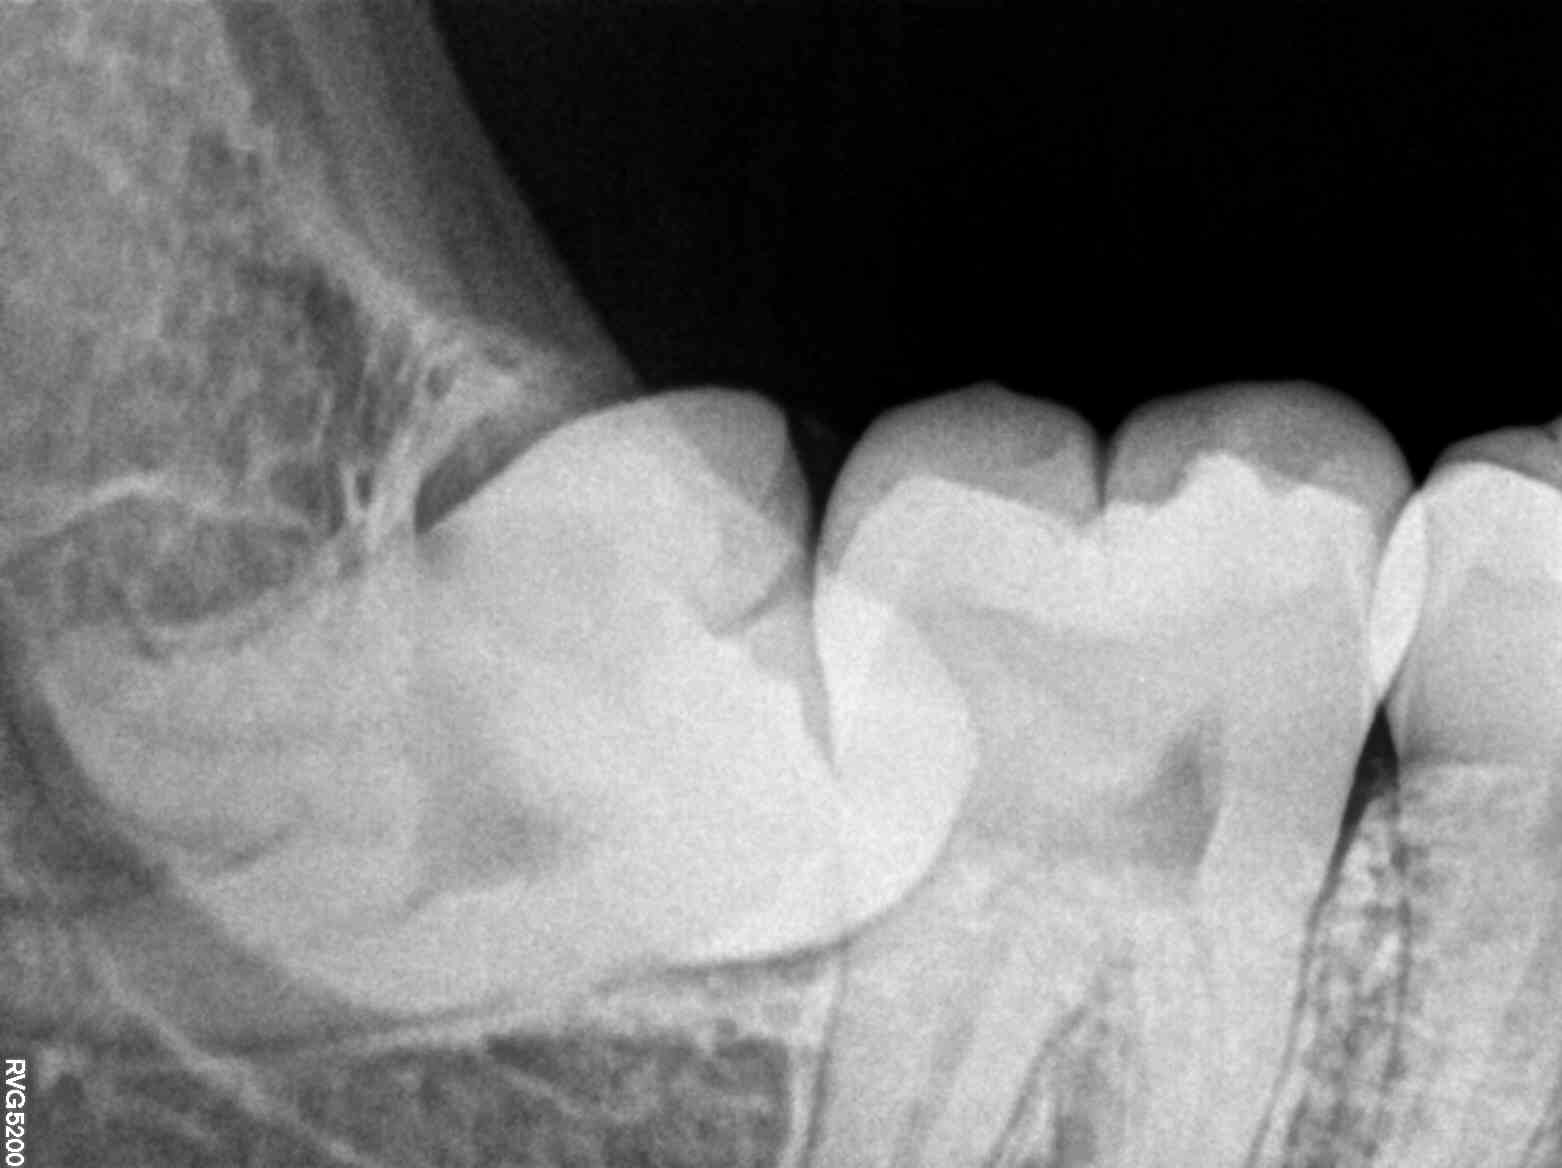

Modern dental x-rays have revolutionized the field of dentistry by providing a clear and detailed view of the teeth and surrounding bone structure. Unlike older x-ray technology, these advanced systems offer higher resolution images, significantly improving a dentist's ability to detect problems early on. For Meera, this meant pinpointing the cause of her discomfort—a small cavity hidden between her back molars that was on the verge of causing a more serious infection.

The process was quick and painless, with the results ready in minutes. As Dr. Rajiv walked Meera through the x-ray images, she was amazed at the clarity and detail. The cavity, which was not visible through a regular examination, was clearly highlighted on the screen. Armed with this knowledge, Dr. Rajiv was able to devise a treatment plan that addressed the issue promptly, saving Meera from potential future pain and costly procedures.